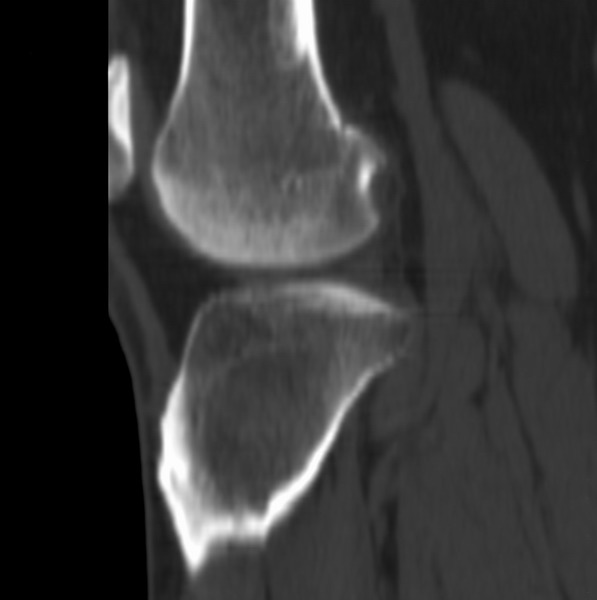

右侧膝关节疼痛一月

男、48

股骨下段、胫骨上段。

1、股骨干骺端病变考虑干骺端纤维性皮质缺损愈后(非骨化性纤维瘤)改变,胫骨近端内生骨瘤(或干骺端纤维性皮质缺损愈后改变);

2、骨关节炎,骨质增生,股骨外侧髁退变性囊肿(关节面软骨下囊肿);

3、髌骨前缘裂纹骨折?